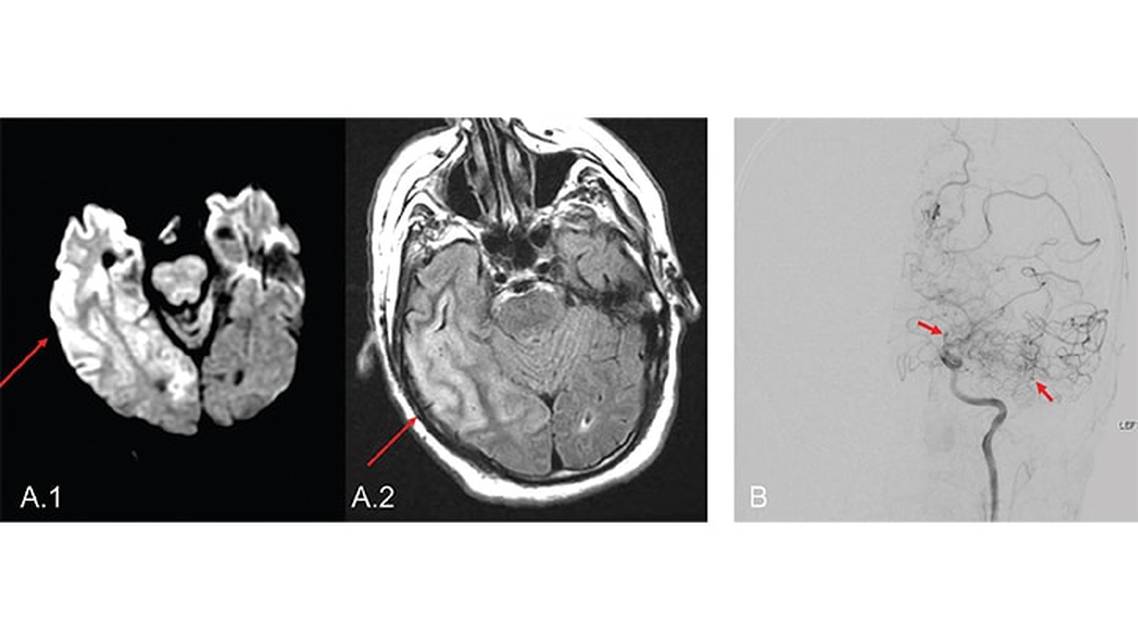

CSF diagnostics in early symptomatic syphilis are typically more abnormal than in asymptomatic meningitis or tertiary neurosyphilis, with a lymphocytic pleocytosis often in excess of 200 cells/mm3 and elevated protein up to 100 to 200 mg/dL3. In tertiary neurosyphilis, the lymphocytic pleocytosis is on a smaller scale between 10 to 75 cells/mm3 and protein levels typically less than 100 mg/dL3, although CSF may also be normal.9 MRI brain imaging findings in neurosyphilis are also variable and may include evidence of infarct or vasculitis, brain atrophy, white matter demyelination and even enhancement in the unilateral or bilateral temporal lobes reminiscent of HSV encephalitis9 (Figure 1). One imaging pattern particularly suggestive of neurosyphilis is the presence of cerebral gummas, which are typically T1-hypointense and T2-iso- or hyperintense, homogenously-enhancing, well-demarcated, and pial-based lesions with or without surrounding edema.9

Definitive diagnosis of CNS TB can be challenging due to the fastidious nature of M. tuberculosis. When suspected, evaluation for signs of pulmonary TB with chest radiograph or CT of the chest should be performed along with a tuberculin skin test (TST) or serum interferon-gamma release assay test when available, though the latter two tests cannot distinguish between latent and active TB.23 In a patient with known or suspected systemic TB and neurologic symptoms, MRI brain with contrast and LP should be performed. On MRI brain scans, TBM typically involves the basilar cisterns, leading to enhancement of the meninges at the skull base.19 Tuberculomas classically appear as ring-enhancing lesions with central areas of hypointensity on T2-weighted images19,21 (Figure 3).